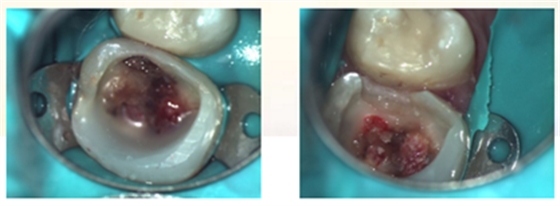

复诊,无不适,去除冠部暂封,试主牙胶尖,拍摄X-ray。

iROOT SP糊剂单尖法根充四根管,SDR树脂髓腔充填,拍摄X-ray,显示根管充填完好。

牙体预备制取26高嵌体工作模型

复诊,无不适,上橡皮障,粘接树脂高嵌体